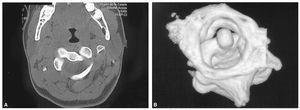

Mujer de 16 años con historia por tortícolis fija aparecida tras cirugía tiroidea; tratada mediante AINE y ortesis cervical blanda, no mejora por lo que a las 10 semanas es enviada a nuestro centro. El diagnóstico, SRCAA tipo I de Fielding, se obtuvo mediante TAC (fig. 6A) con reconstrucción tridimensional (fig. 6B) utilizándose el mismo protocolo de tratamiento que en los otros pacientes, llegando a 14 kg; a las 3 semanas la movilidad era simétrica y la TAC confirmó la reducción completa de la divergencia rotacional (fig. 7), inmovilizándose con halo-yeso 6 semanas y ortesis cervical blanda otras 6 semanas. Dos años después, la función es completamente normal, no habiendo presentado episodios de cervicalgia ni tortícolis.

Figura 6. A: tomografía axial computarizada convencional en la que se puede apreciar la rotación de 32° entre C1-C2 en el paciente n.O 3. B: la reconstrucción tridimensional nos muestra la deformidad típica de rotación y pinzamiento C1-C2.

El diagnóstico radiológico es difícil, ya que la deformidad y el dolor impiden obtener buenas proyecciones, así en la radiografía anteroposterior simple se superpone la cabeza, y en la lateral se puede observar una falta de paralelismo entre el cráneo y la columna; la radiografía transoral de odontoides puede ser de gran valor, mostrando una asimetría entre el diente del axis y las masas laterales del atlas con posible pinzamiento de las facetas8. Se ha sugerido la utilización de la TAC dinámica, con rotación a izquierda y derecha de la cabeza, pero en situación de SRCAA la movilización es dolorosa, por lo que difícilmente se obtendrá la cooperación del paciente, pudiendo llevar a confusión en el diagnóstico13. En una tortícolis aguda no parece estar indicado el estudio con TAC14,15, pero en casos persistentes con sospecha de SRCAA es muy útil para confirmar el diagnóstico, ya que mostrará la divergencia rotacional C1-C2 que se puede cuantificar midiendo la angulación existente entre las líneas que unen las apófisis transversas del atlas y del axis (fig. 2)16. En la TAC tridimensional se puede apreciar la deformidad rotacional con el desplazamiento completo de las facetas articulares, la situación asimétrica de la odontoides en el arco anterior del atlas --que asimismo puede orientar sobre la integridad del ligamento transverso-- y el desplazamiento de la espinosa de C24. La RMN es un buen complemento, ya que puede informar de interposición de partes blandas7, así como de la posible lesión del ligamento transverso17, por lo que en caso de duda puede indicar la necesidad de estabilización quirúrgica. En nuestra serie, ante una sospecha de SRCAA, se utilizó la TAC simple como método diagnóstico (fig. 2 y 4A), completándose en el tercer caso con reconstrucción tridimensional (fig. 4B) en la cual fueron muy evidentes las alteraciones torsionales del complejo atlantoaxial.